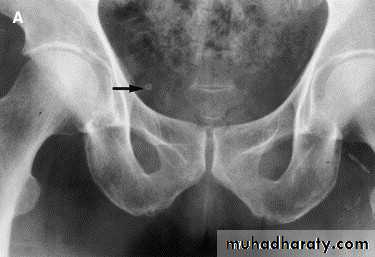

- Over 90% of calculi are radiopaque on plain films and virtually all on CT as very sensitive for detection of calculi, even those that appear radiolucent on plain film.- Most of these stones are a mixture of calcium oxalate and phosphate.

- Only pure uric acid and xanthine stones are radiolucent on plain x-ray but CAN be identified by CT or US , uric acid stones are associated with increased uric acid excretion in urine as in gout.

Ddx of stone on KUB :

1. Gall stone2. Calcified LN , cartilage ,fibroid,

3. Phlebolith: round, lucent centre.

Infestation by s.hematobiumCalcification is most important feature, mainly in bladder & lower ureters , but may involve whole ureters .